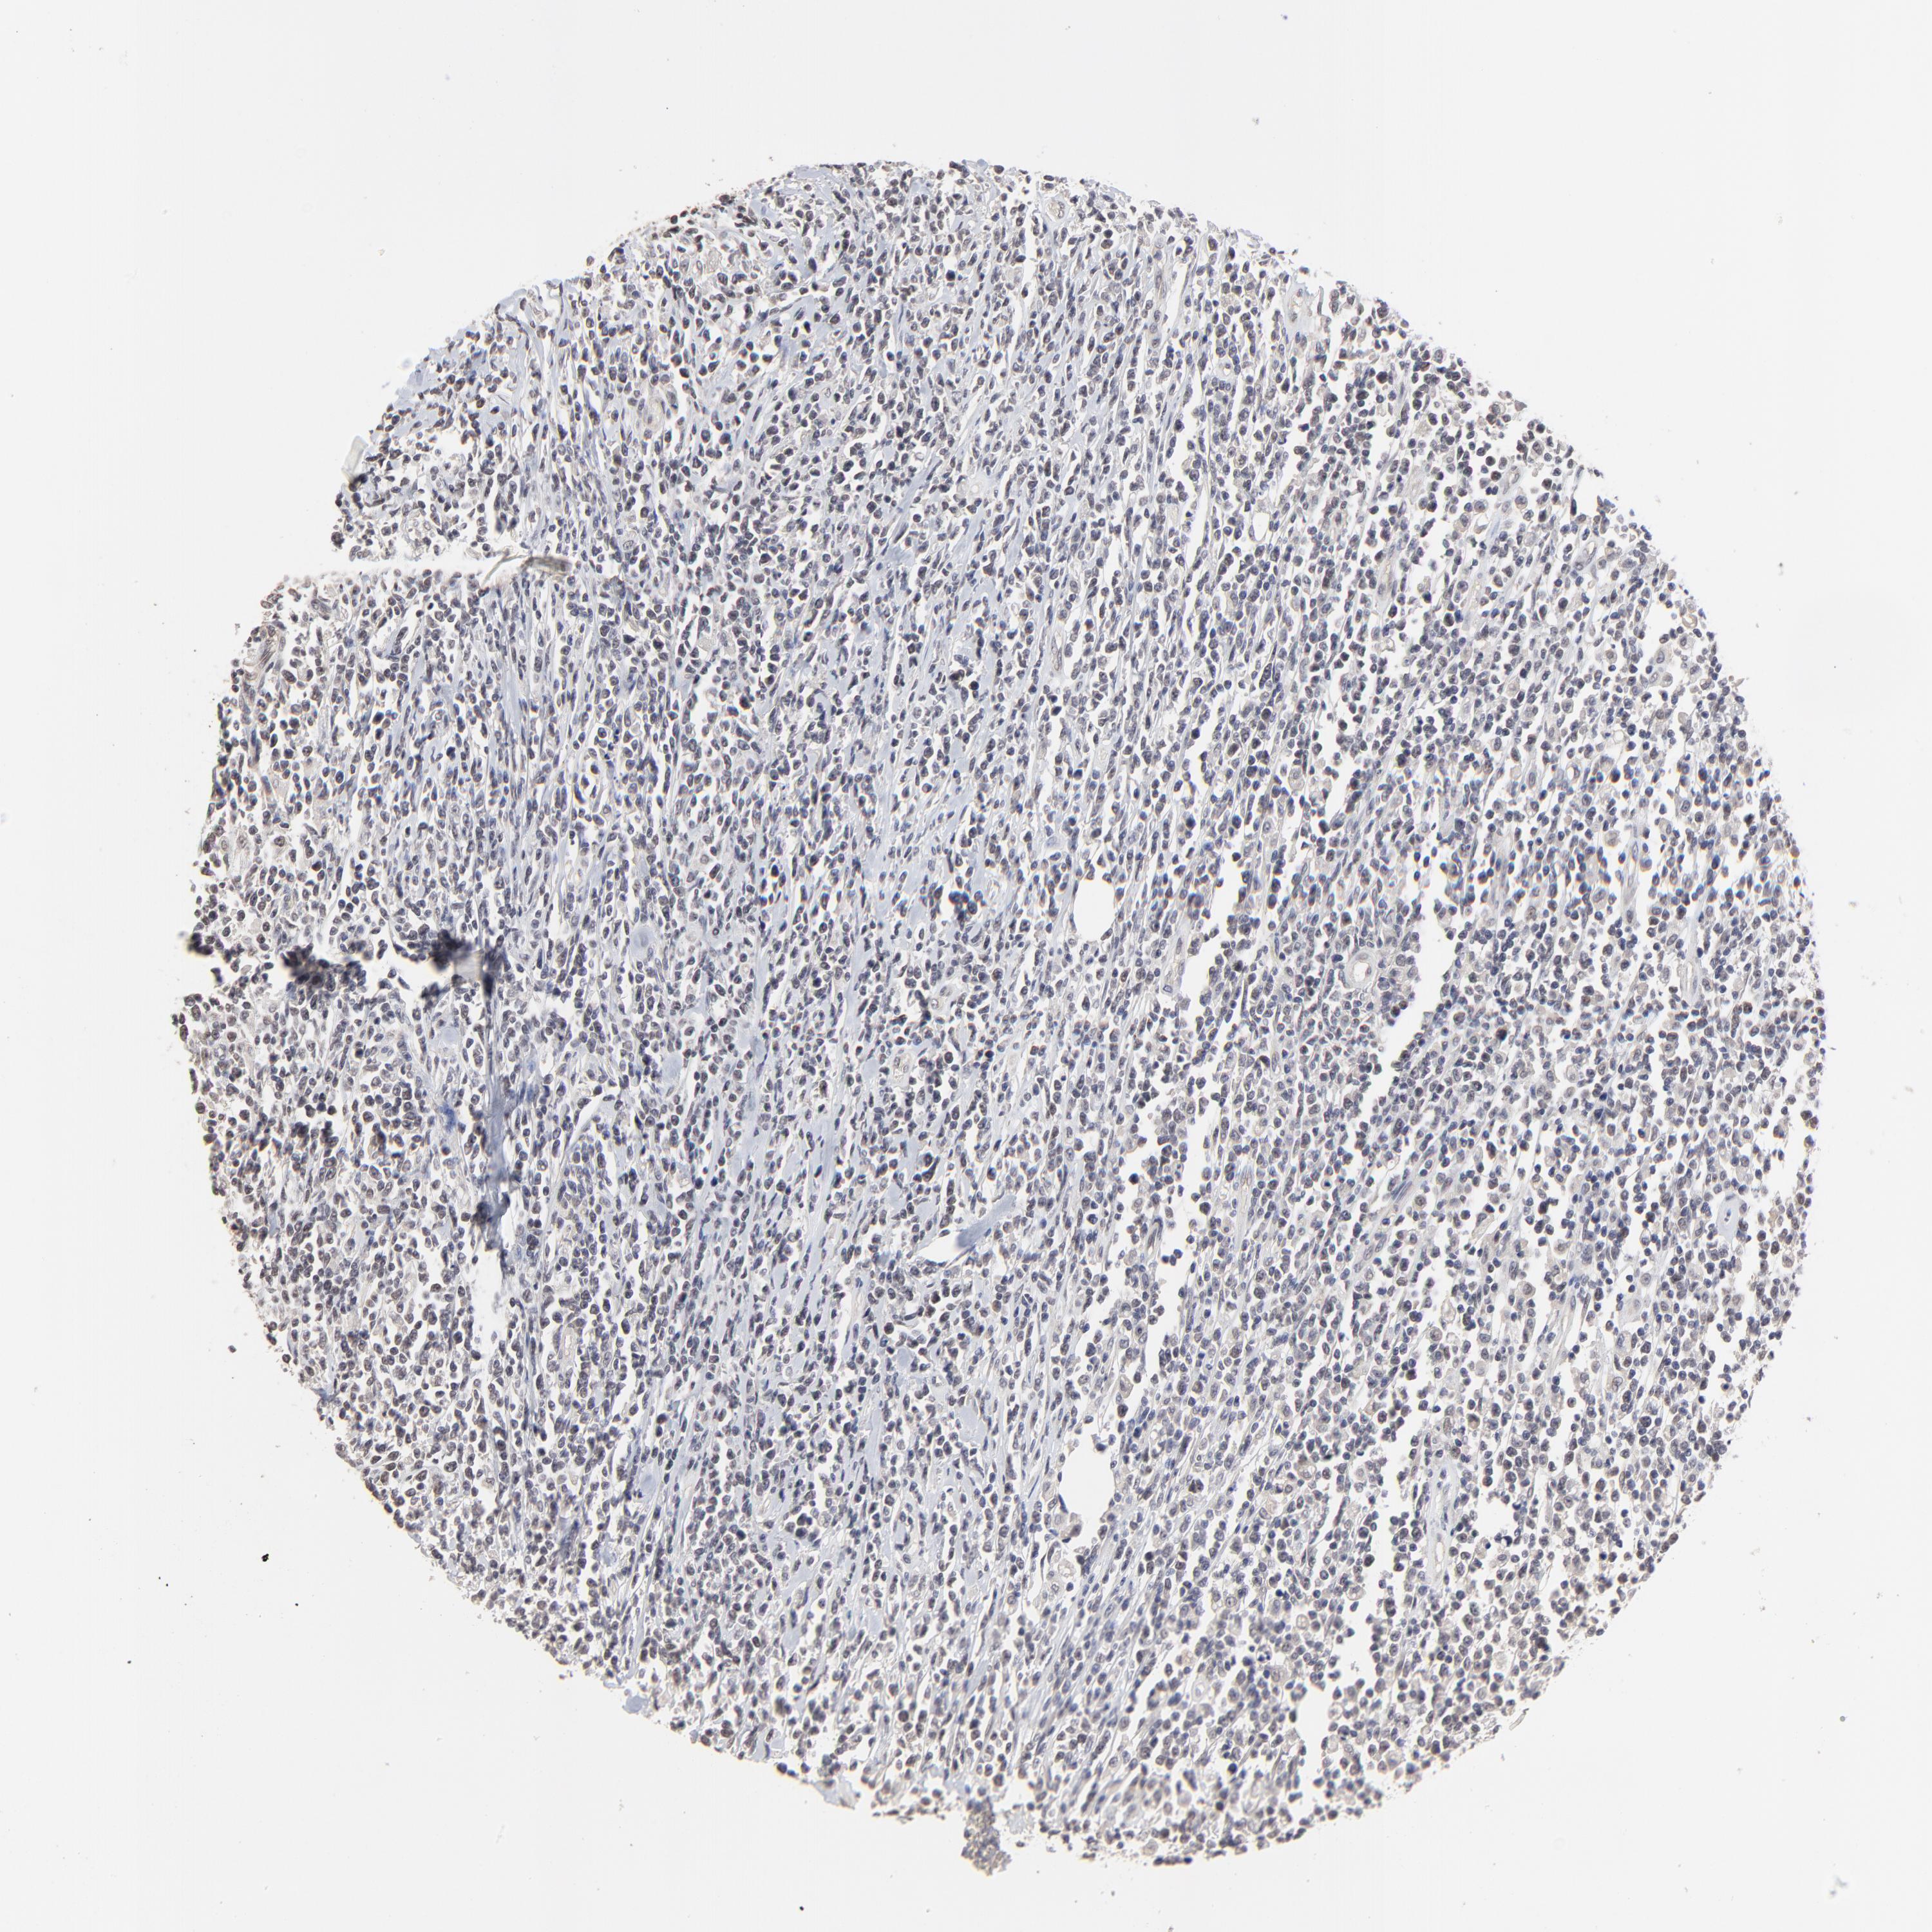

LYMPHOMA - Protein expressioni

A mouse-over function shows sample information and annotation data. Click on an image to view it in a full screen mode. Samples can be filtered based on level of antibody staining by selecting one or several of the following categories: high, medium, low and not detected. The assay and annotation is described here.

Antibody stainingi

Antibody staining in the annotated cell types in the current human tissue is reported as not detected, low, medium, or high, based on conventional immunohistochemistry profiling in selected tissues. This score is based on the combination of the staining intensity and fraction of stained cells.

Each image is clickable and will lead to virtual microscopy that enables deeper exploration of all samples and also displays staining intensity scores, fraction scores and subcellular localization as well as patient and tissue information for each sample.

Antibody HPA003093

Malignant lymphoma, non-Hodgkin's type, High grade

Hodgkin's disease, NOS

Malignant lymphoma, non-Hodgkin's type, Low grade